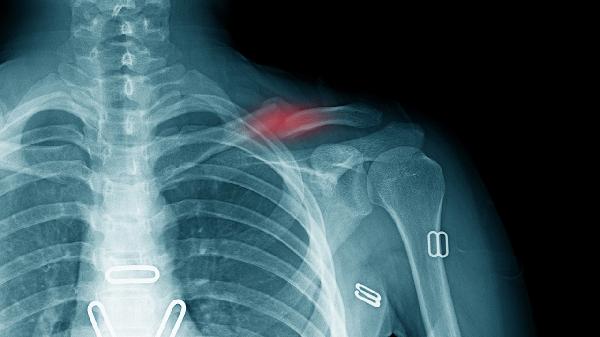

2、足部外傷如扭傷或骨折也會導致腳掌疼痛,外傷后腳掌出現(xiàn)持續(xù)疼痛、腫脹和淤血。處理急性外傷可以使用RICE原則,包括休息、冰敷、壓迫和抬高患肢。對于嚴重骨折可能需要石膏固定,石膏固定時間通常為6-8周。物理治療可以幫助恢復功能,包括關節(jié)活動度練習和肌肉力量訓練。